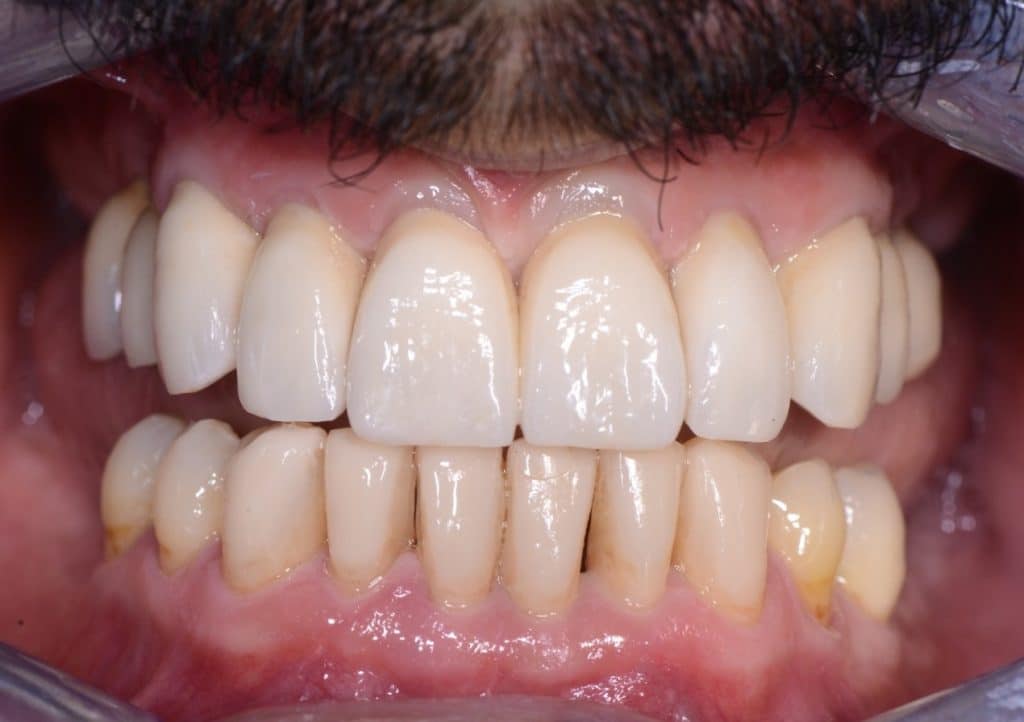

Post-operative view: layered cubic zirconia single crowns at the maxillary arch and injected direct composite restorations at the mandibular arch.